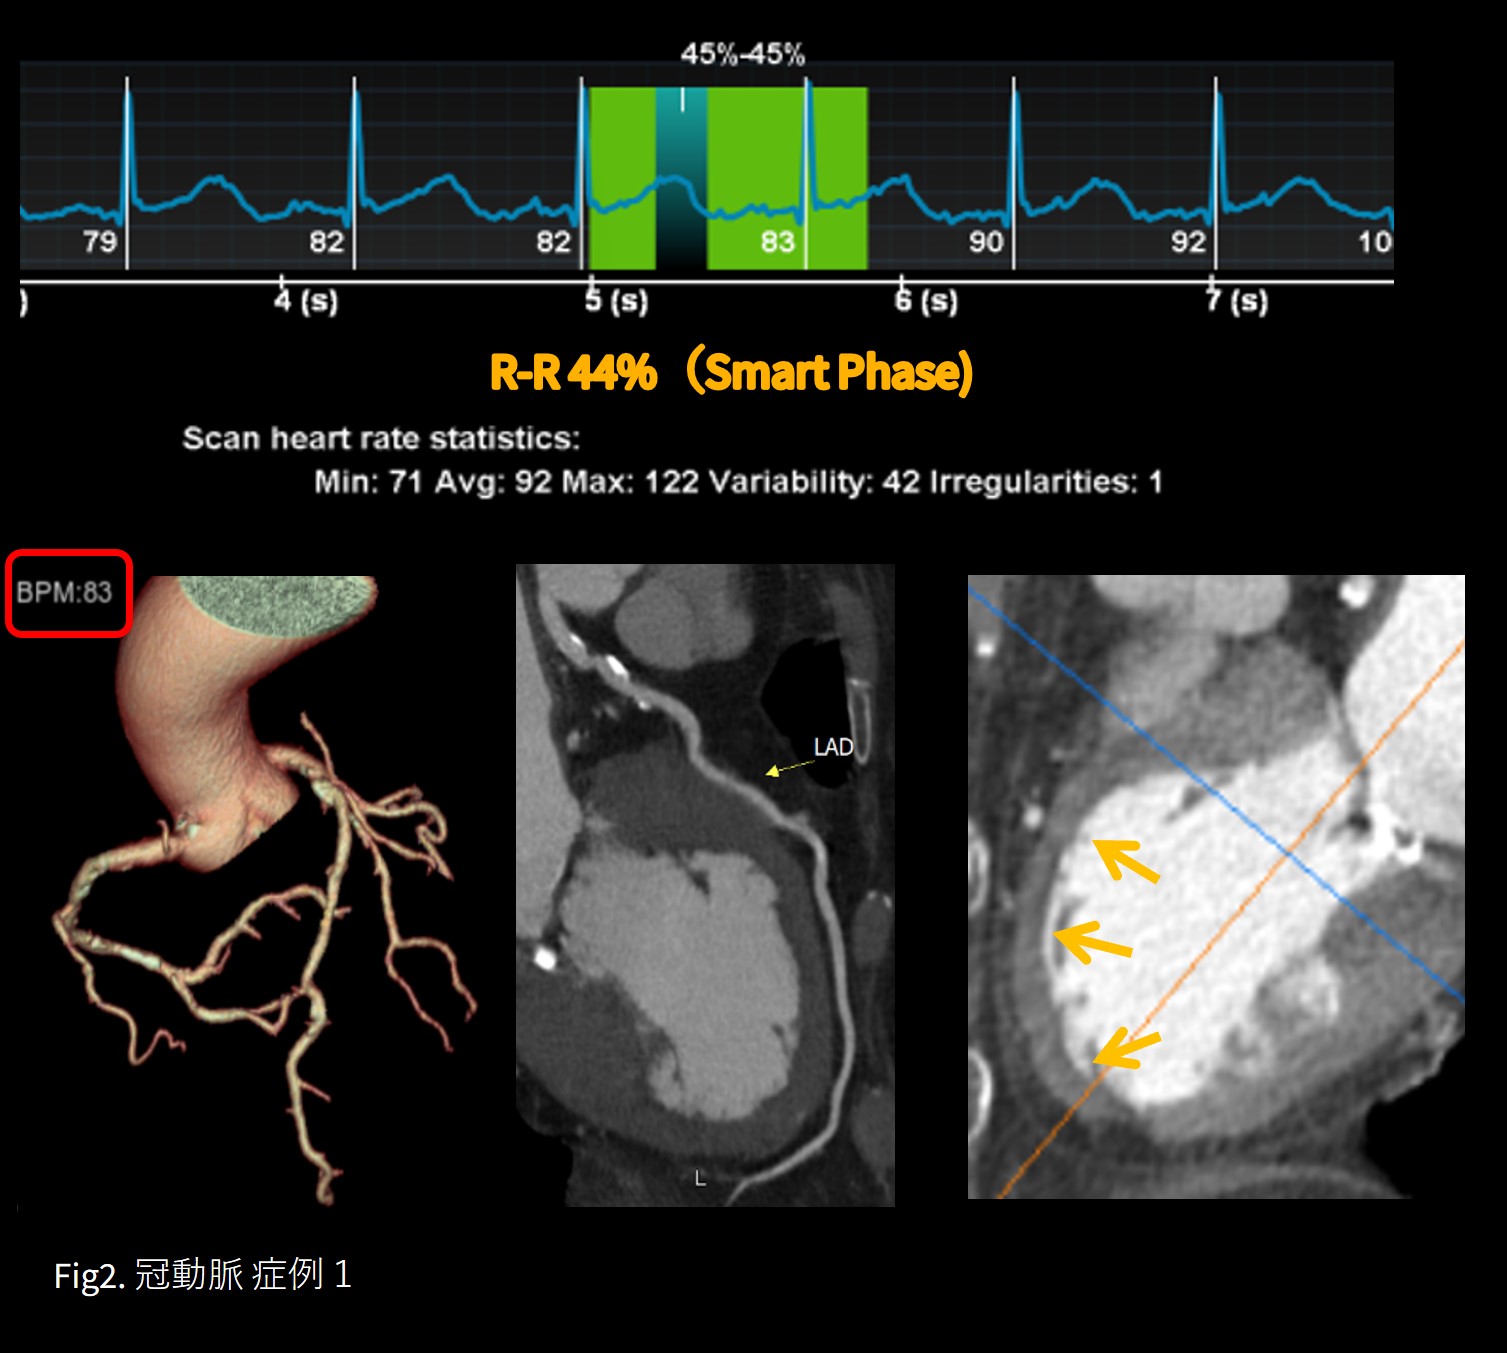

症例 1 たこつぼ形心筋症

心拍数83  洞調律 認知症/不穏 (息止め不可能) 発熱/COVID19(デルタ株)疑い

本症例は高心拍、息止め困難であったが、ワイドカバレッジによる1心拍撮影、回転速度0.28s/rotの高時間分解能に加え、Smart cardiacとSSF2の恩恵で鮮明な画像を安全且つ迅速に救急現場に提供する事ができた。 Revolution CTの「類い稀なる汎用性」は有事にも強い事を目の当たりにした一例である。(Fig.2)

胸部症状を訴え路上で倒れている所を発見され救急搬送された。不穏で高度な認知症があり、体温38.5℃ SpO2=94%(RA)。心電図は胸部誘導で広範囲にT波が陰転化。採血データは心筋トロポニンI (11.060 ng/ml)とともにD-ダイマー( 2.8 μg/ml)も異常高値であった。通常であれば緊急カテーテル検査の適応であるが、不穏で安静が保てず酸素マスクが装着できない、かつ、デルタ株が猛威を振るっていた時期で、まだ迅速診断キットなど普及しておらずCOVID19の感染も不明のまま安全にカテーテル検査を行う事が躊躇される症例であった。幸いにも、血圧は安定しており胸部症状も消失していたため、冠動脈CTに白羽の矢がたった。撮影時、HR80台の頻拍、息止めは全く不可能であったが出来上がった画像は鮮明に冠動脈を描出。LADを含め冠動脈には一切有意狭窄は認めず、また肺塞栓・大動脈解離も否定する事が出来た。壁運動は心尖部が著明な壁運動低下を認め心基部は過収縮だった。典型的なたこつぼ型心筋症である。患者は陰圧管理可能なICU個室に入り経過観察のみで元気に独歩退院となった。